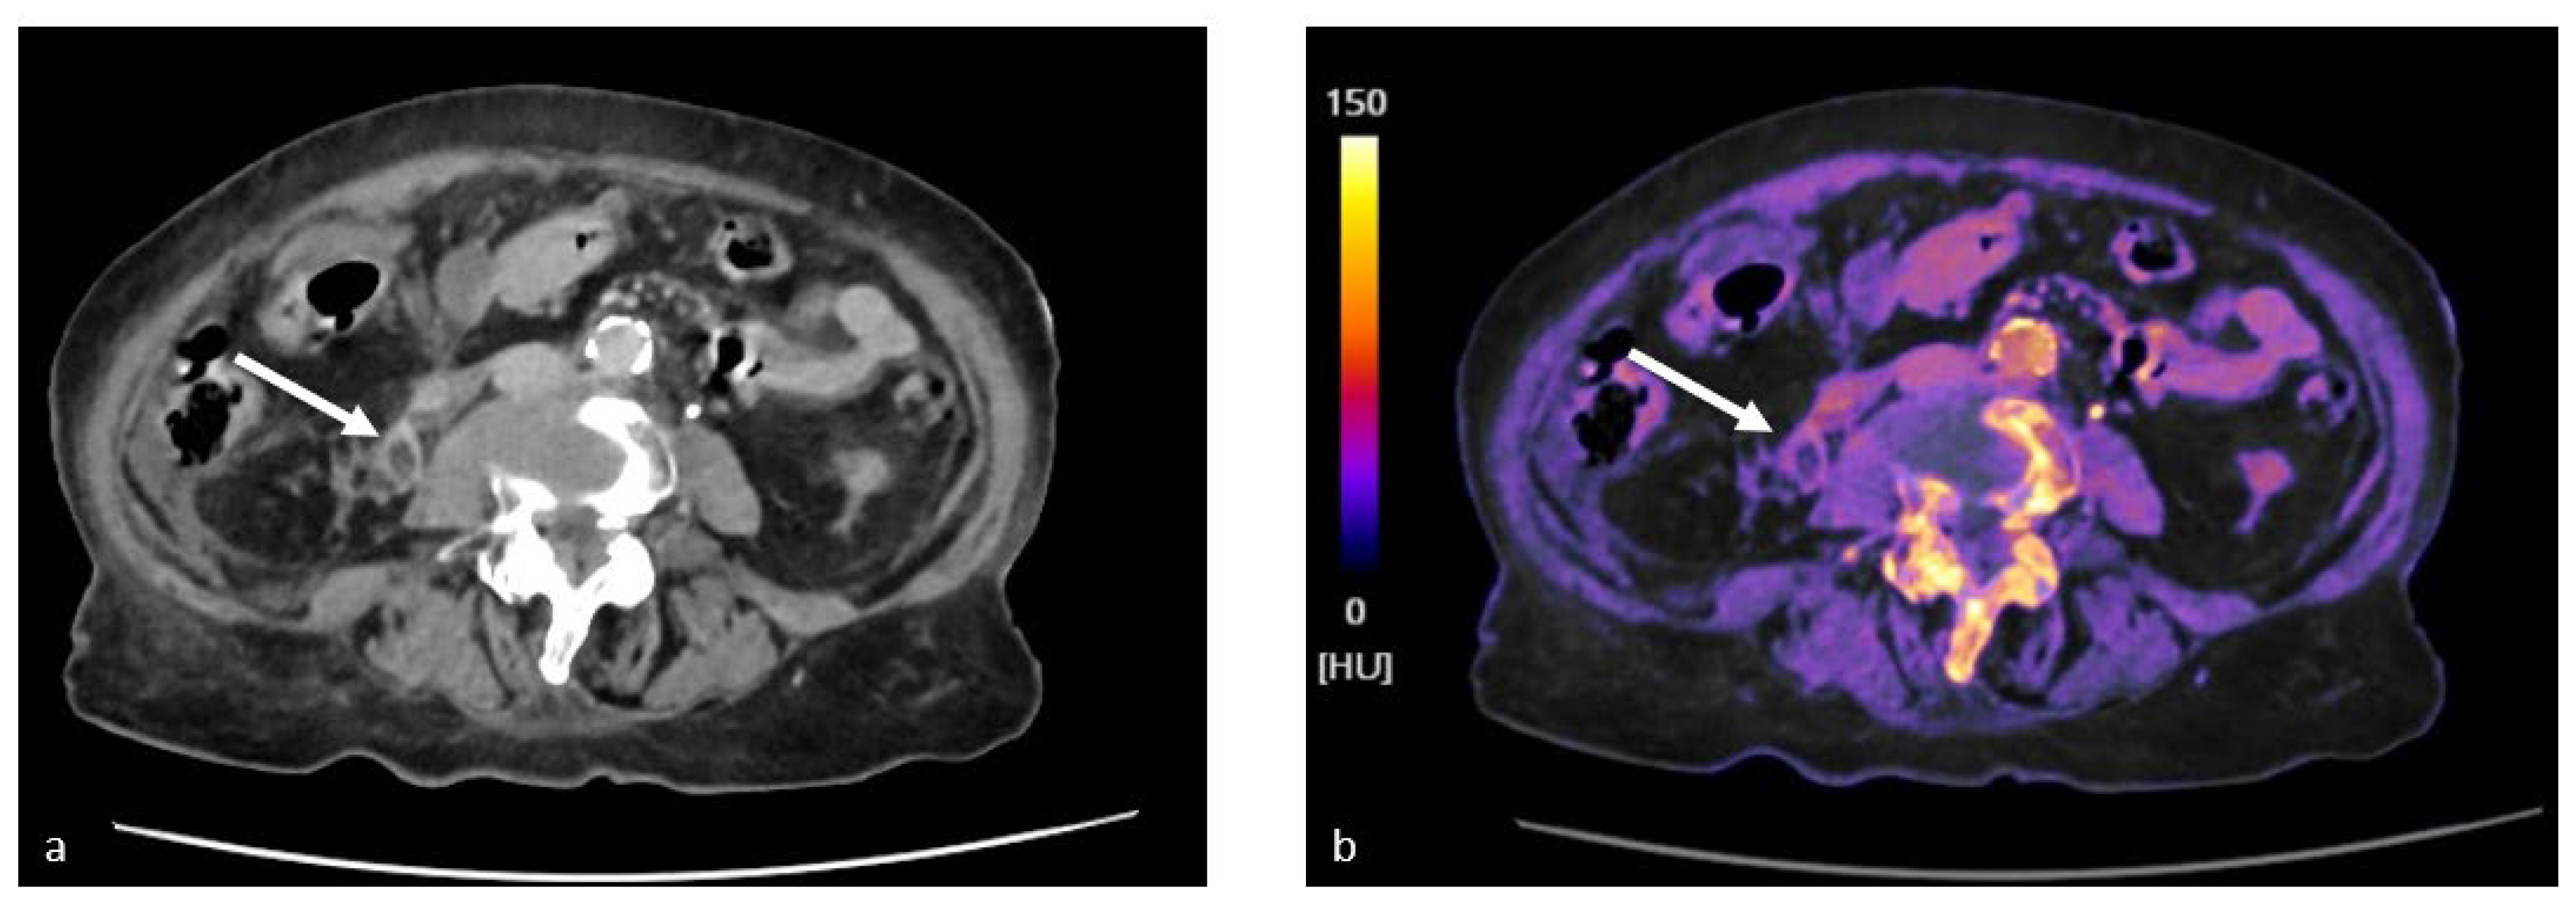

4.3. Study of the Bladder and Ureters